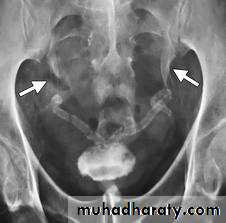

Schistosomiasis

Infestation by s.hematobiumCalcification is most important feature, mainly in bladder & lower ureters , but may involve whole ureters .

In early stage inflammation may cause cobble stone appearance.

Bladder capacity not affected.Ddgx of bladder calcification :